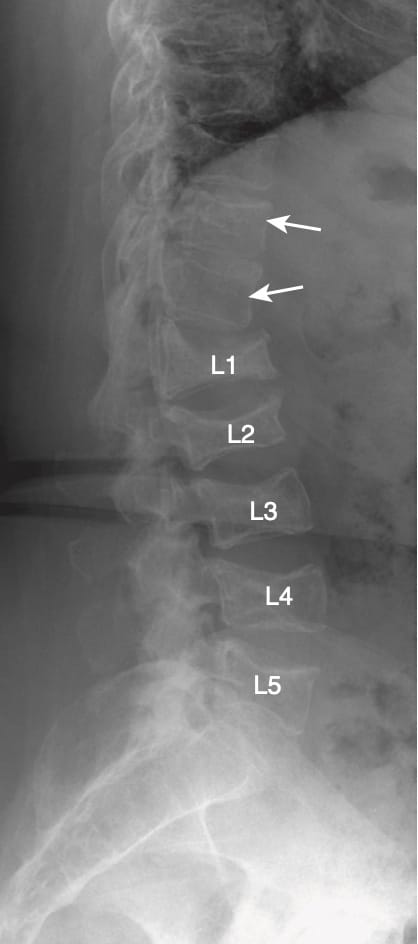

- Ở cột sống, di căn có thể dẫn đến gãy xương do nén. Di căn có xu hướng phá hủy thân đốt sống, bao gồm cả mặt sau và các cuống, khác với gãy xương do nén trong loãng xương trong đó phần sau thân đốt sống và cuống cung vẫn còn nguyên vẹn.

- Cột sống cũng là vị trí thường gặp của bệnh đa u tủy, một bệnh lý ác tính nguyên phát phổ biến nhất của xương. Đa u tủy được biết đến với xu hướng tạo ra các tổn thương hầu hết là tiêu xương. Một trong những dấu hiệu đặc trưng của đa u tủy là loãng xương, do đó đa u tủy có thể kết hợp với loãng xương cột sống lan tỏa và gãy xương do nén ở nhiều đốt (Hình 12).

- Với thâm nhiễm tân sinh của tủy xương, có sự giảm tín hiệu bình thường cao của đốt sống trên các hình ảnh T1W, và thường có tín hiệu cao trên các hình ảnh T2W (Hình 14).

- Không giống như gãy xương do nén do loãng xương (có xu hướng không ảnh hưởng phần sau của thân đốt sống trong khi làm xẹp phần trước và giữa), di căn cột sống thường ảnh hưởng đến toàn bộ thân đốt sống, bao gồm cả phần sau.